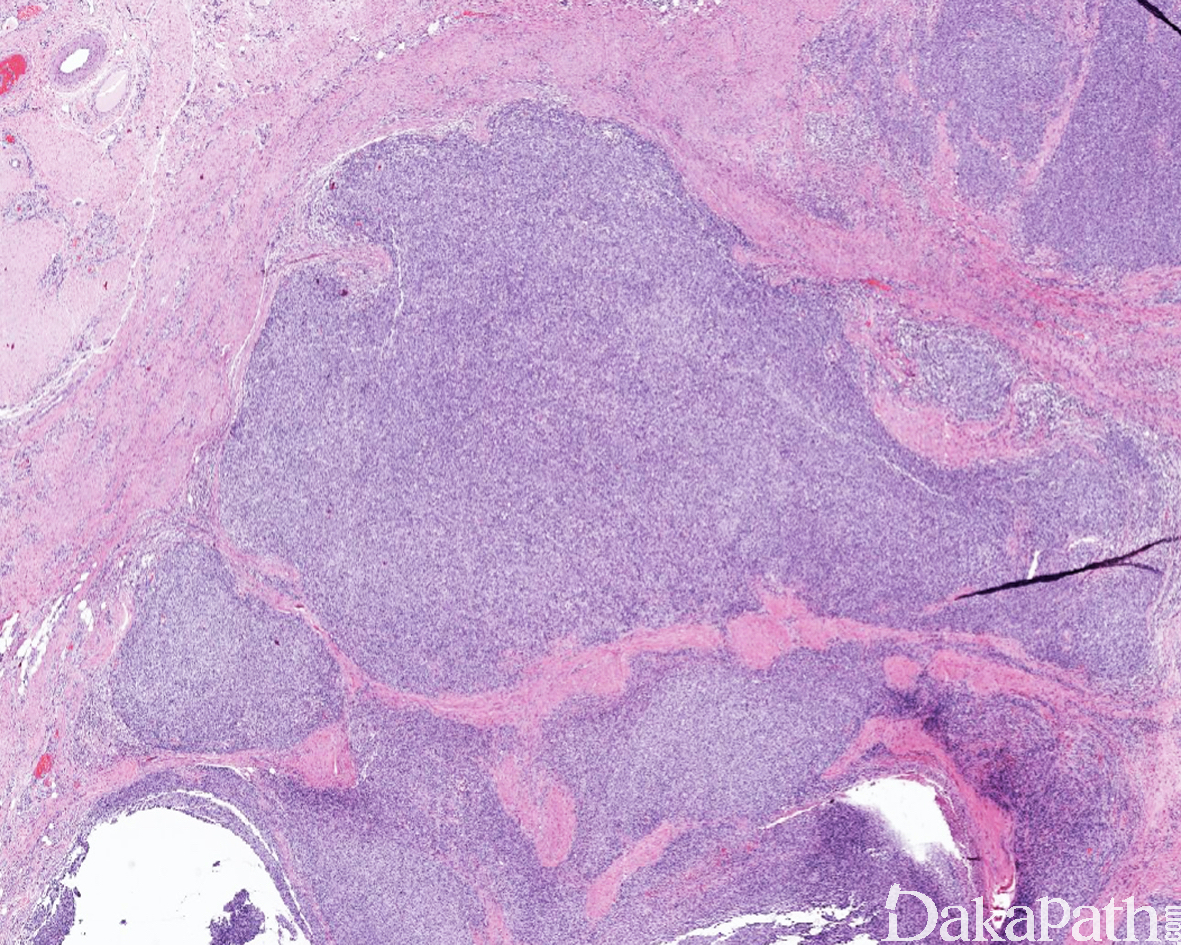

低倍镜下显示实性成片的小到中等大的圆细胞增生,约 1/3 可见胶原纤维分隔的结节状或模糊结节状生长;少见的结构特征包括交错束状或网状排列

约 1/3 可见不同程度的黏液性间质改变;

绝大多数肿瘤可见多灶性的地图性坏死。